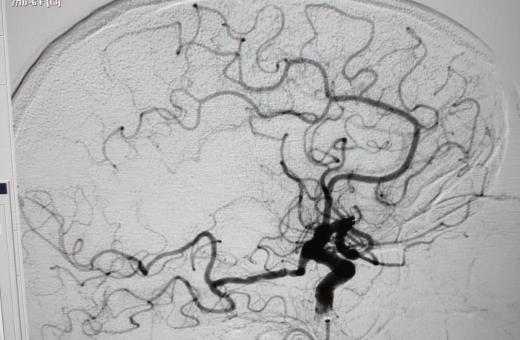

12/06/2020 El Trueta amplia als caps de setmana la neuroradiologia intervencionista per fer tractaments de teràpia endovascular a pacients amb un ictus isquèmic agut